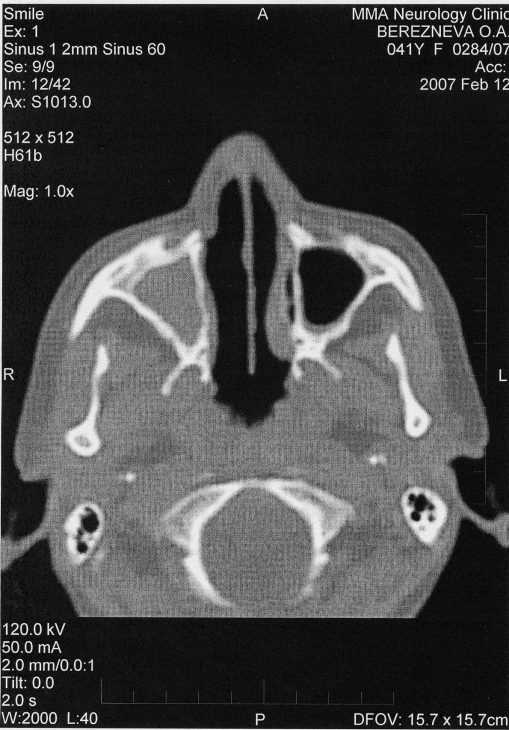

Гранулематоз Вегенера Автор Полина Корректор | дата обновления 13.02.2015 Facebook Мой мир Вконтакте Одноклассники Google+ Гранулематоз Вегенера Рубрика: Поделись в соцсетях Вконтакте Facebook Одноклассники Google+